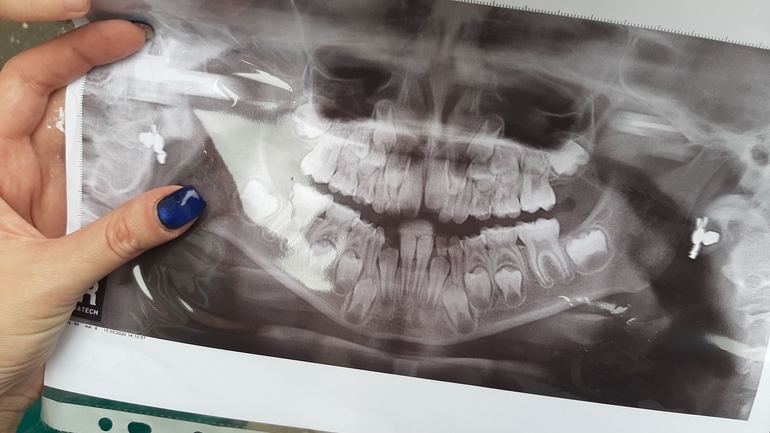

Вырвали ребенку 2 верхние единички пару недель назад. Вчера делали ОПТГ....

На фото видно как растворились корни на некоторых зубах, хотя они даже не шатаются.